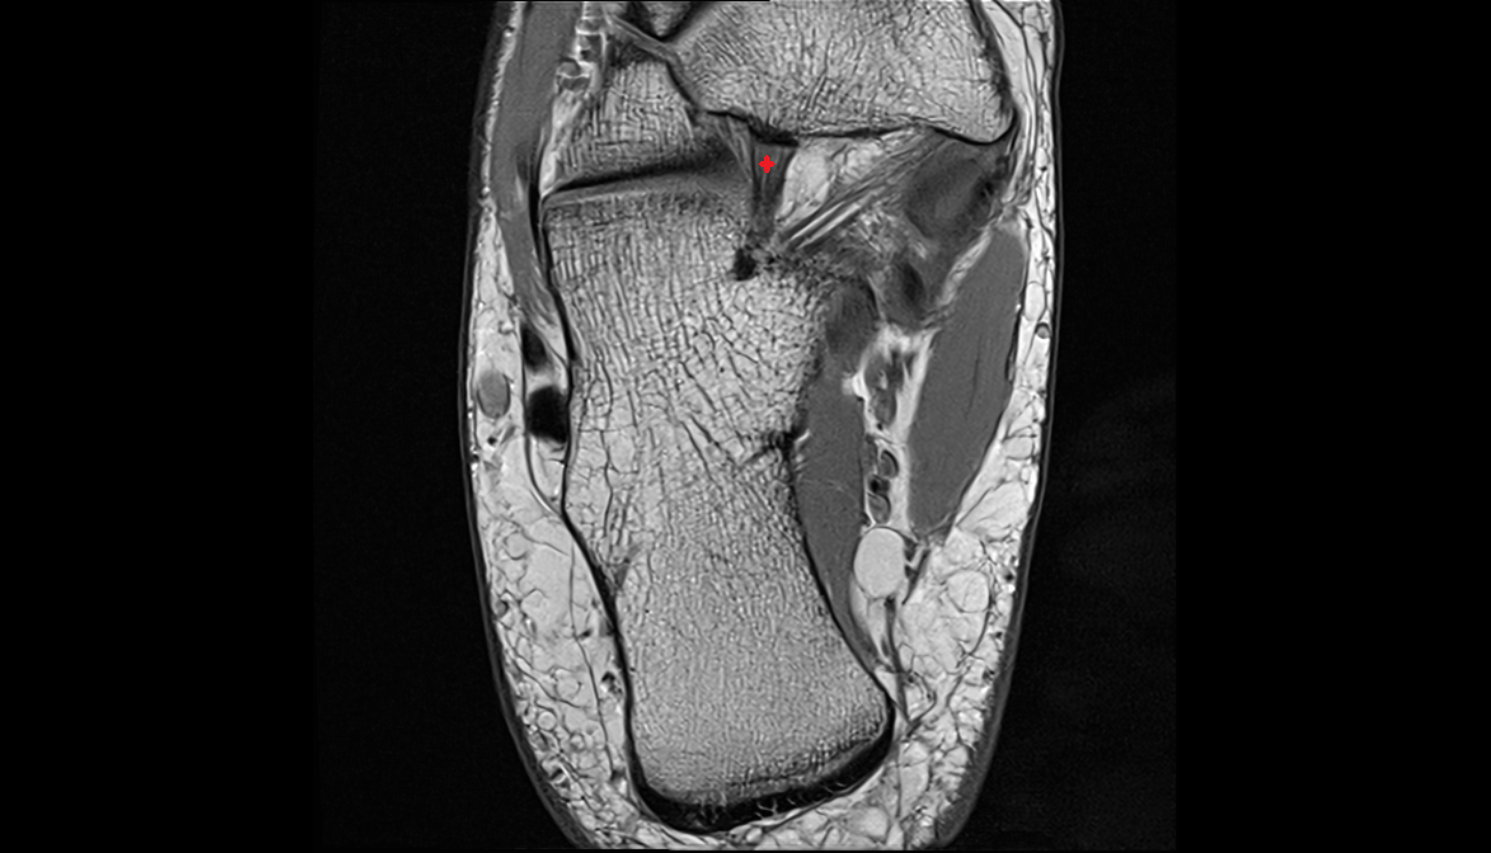

- Talus

- Calcaneus

- Medial malleolus

- Lateral malleolus

- Ankle joint

- Tibialis posterior muscle

- Flexor digitorum longus muscle

- Flexor hallucis longus muscle

- Tibialis posterior tendon

- Achilles tendon